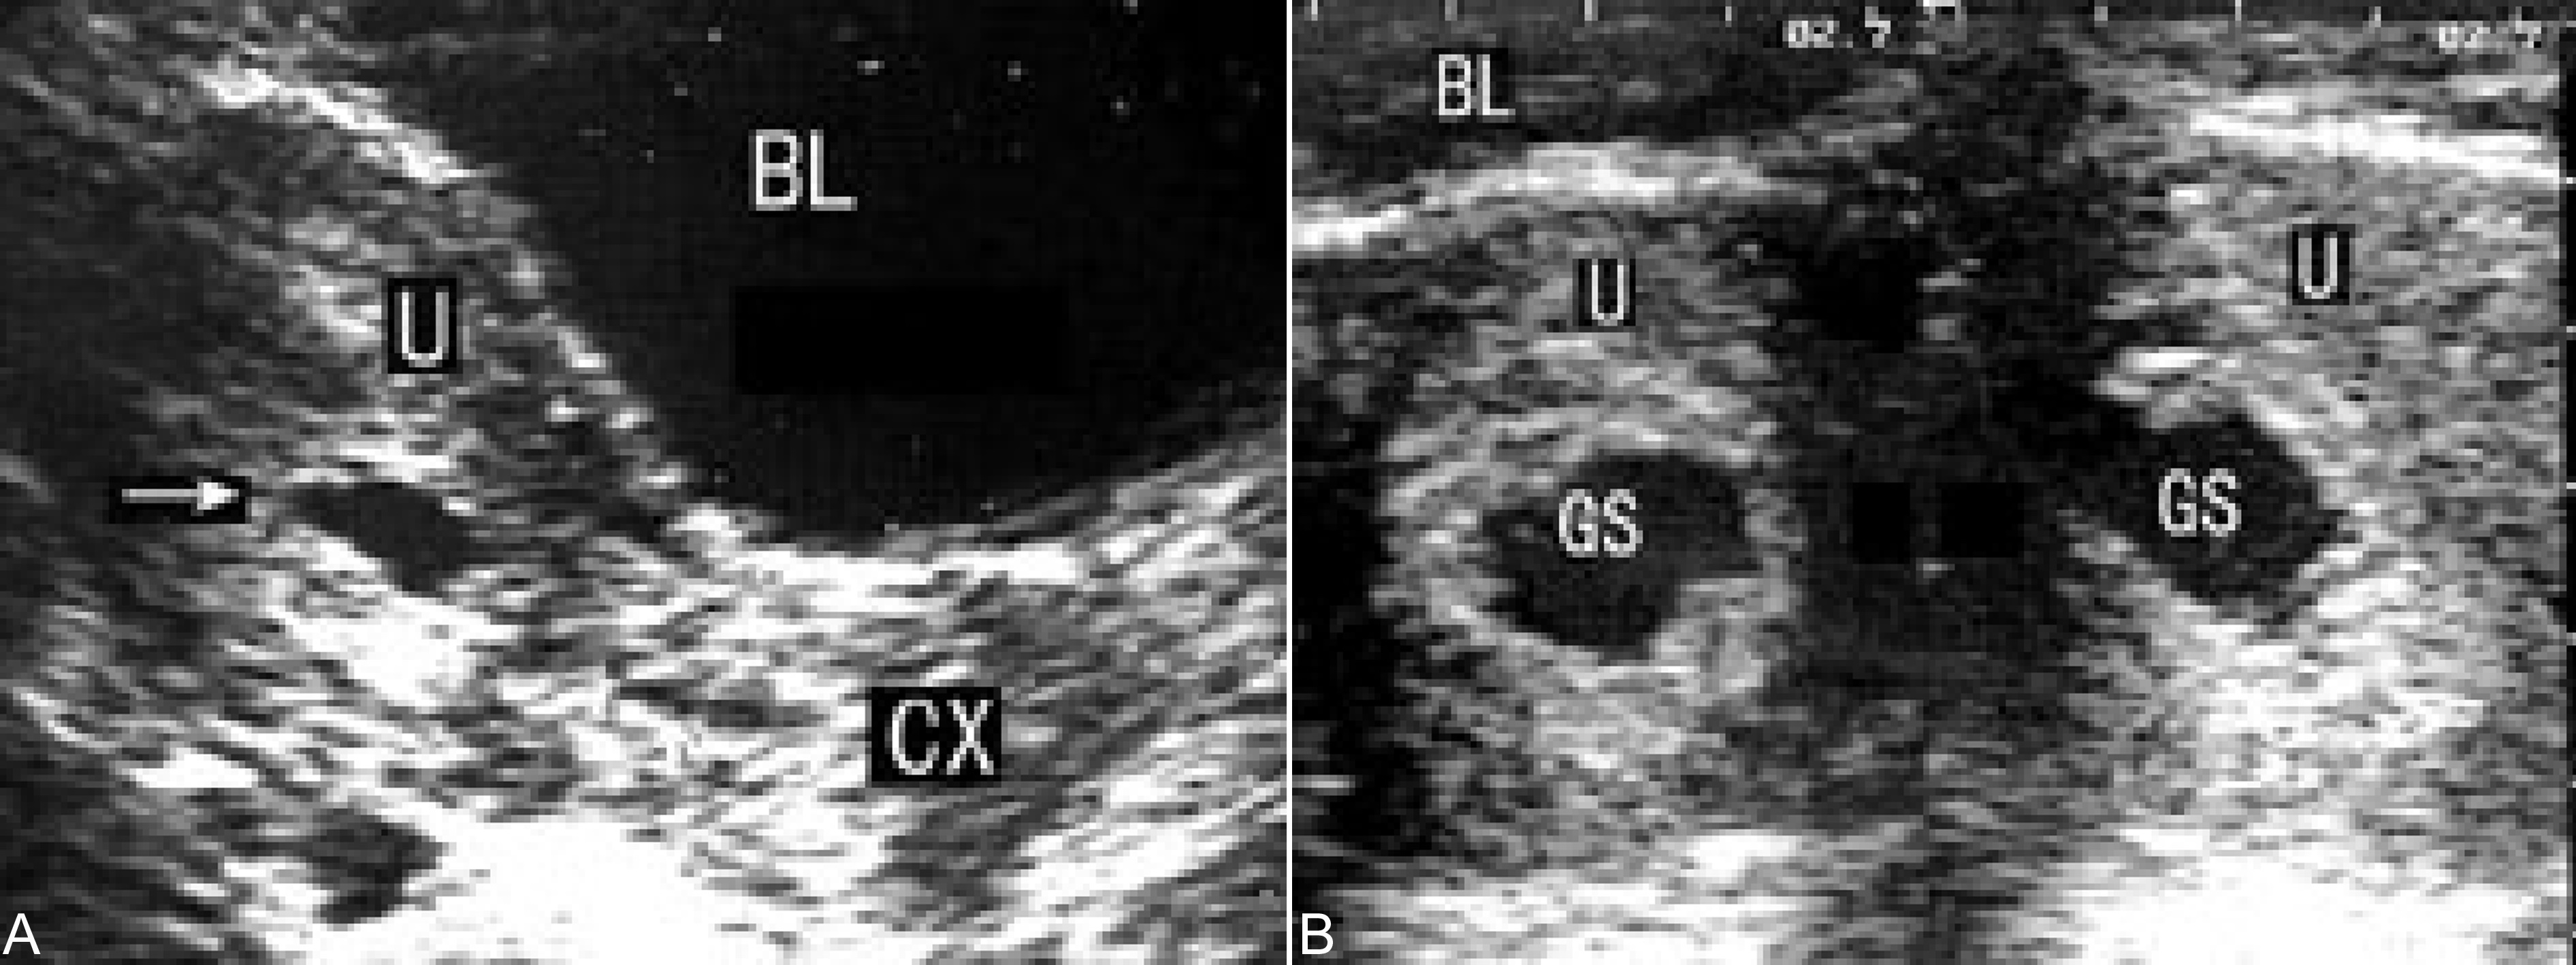

子宫小于停经月份,妊娠囊消失,宫腔内残存不规则无回声区或低回声区,分布不均匀(图4),或可见死亡的胚胎或胎儿回声,或可显示胎儿的骨骼强回声。结合病史可作出不全流产的诊断。

图4 不全流产声象图:胎体已排除,箭头指示宫腔内及宫颈管处仍有胚胎残留物

胎盘、绒毛组织等残留时显示为宫腔内较低而模糊的不规则回声区,随着时间的延长,其回声逐渐增强,边缘逐渐清晰,但回声仍不均匀。人工流产后妊娠产物的残留亦显示同样的回声。